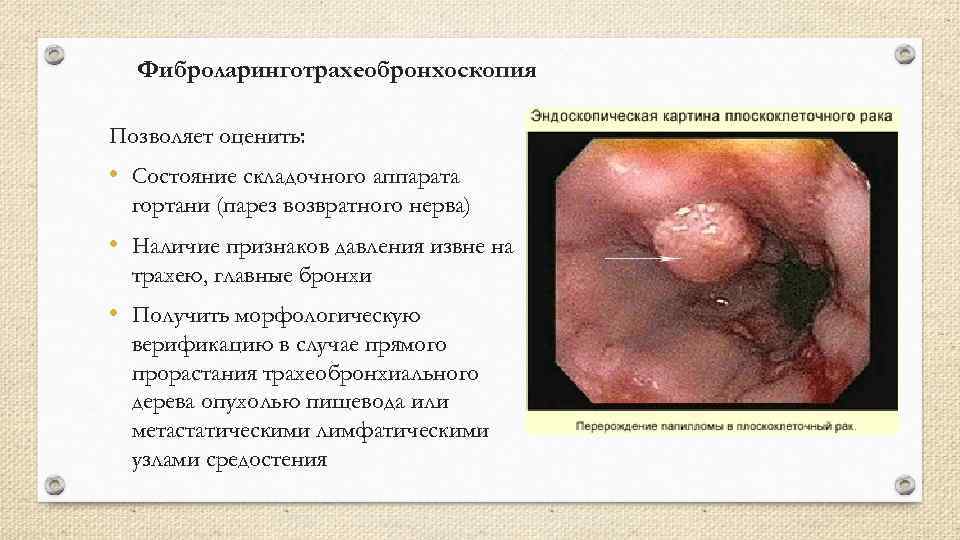

Фиброларинготрахеобронхоскопия Позволяет оценить: • Состояние складочного аппарата гортани (парез возвратного нерва) • Наличие признаков давления извне на трахею, главные бронхи • Получить морфологическую верификацию в случае прямого прорастания трахеобронхиального дерева опухолью пищевода или метастатическими лимфатическими узлами средостения

Фиброларинготрахеобронхоскопия Позволяет оценить: • Состояние складочного аппарата гортани (парез возвратного нерва) • Наличие признаков давления извне на трахею, главные бронхи • Получить морфологическую верификацию в случае прямого прорастания трахеобронхиального дерева опухолью пищевода или метастатическими лимфатическими узлами средостения